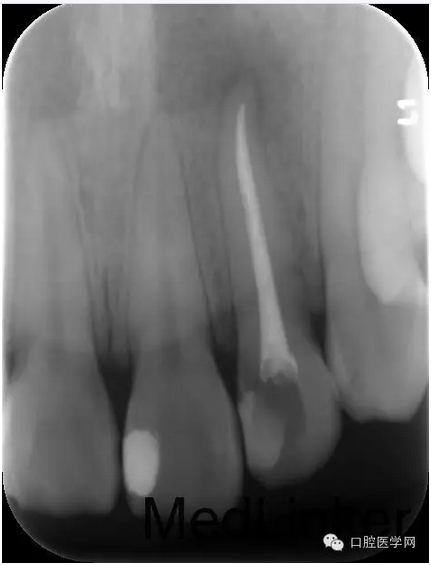

第四次:復(fù)診無不適。叩診無不適,無松動(dòng)。復(fù)查X線片,根尖密度減低區(qū)明顯減小,玻璃離子體部分去除,樹脂充填,調(diào)牙合,拋光。醫(yī)囑待18周歲后行冠永久修復(fù)。